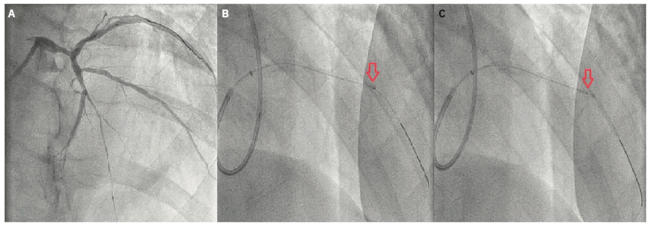

A 65-year-old male presented with a few days of productive cough, progressive fatigue, worsening scrotal edema, and high-grade fever. His past medical history included essential hypertension, tobacco abuse, ischemic cardiomyopathy with a left ventricular ejection fraction (LVEF) of 20%, and severe multivessel coronary artery disease (CAD) involving the left main (LM) (80%), mid left anterior descending artery (LAD) (100%), and distal right coronary artery (RCA) (90%). Vital signs at presentation were notable for hypotension and sinus tachycardia. Physical exam showed 2+ pitting edema of the lower extremities, significant scrotal edema, and inspiratory and expiratory wheezes on auscultation. Laboratory test results were notable for troponin elevation of 0.12 ng/mL and BNP of 7722 pg/mL. Creatinine was elevated at 1.74 mg/dL, which was above the patient’s baseline. An electrocardiogram (EKG) showed inferior Q waves, widespread T wave abnormalities, a right bundle branch block, and a left posterior fascicular block (Figure 1). The chest x-ray showed cardiomegaly without pulmonary infiltrates/consolidation. An echocardiogram showed a severely enlarged left ventricle with a left ventricular ejection fraction of 15%-20%. During his hospital stay, the patient developed cardiogenic shock requiring short-term inotropic support with dobutamine. After stabilization, the patient underwent a coronary angiogram, which showed progression of his CAD with a 90% distal LM stenosis, mid-LAD chronic total occlusion (CTO), and a 99% distal RCA lesion. In the past, the patient had elected not to pursue invasive management and was treated only medically. This time, the patient was willing to consider any treatment option, so cardiothoracic surgery was consulted. The patient was not found to be a good candidate for surgical revascularization. Before discharge, the patient underwent successful percutaneous coronary intervention (PCI) of the RCA with drug-eluting stent (DES) placement. Two weeks later, he presented for staged PCI of the LAD CTO. For the procedure, right radial access was utilized. Dual access was not obtained due to the absence of significant right-to-left collaterals. The LM ostium was engaged with a 6 French Launcher Extra Backup (EBU) 3.5 guide catheter (Medtronic). Initially, the procedure proceeded according to the plan. We were able to cross the LAD CTO without significant difficulties using a Prowater .014-inch, 180 cm coronary guide wire (Abbott Vascular) (Figure 2A). Unfortunately, we were unable to advance further interventional equipment into the lesion. Eventually, we managed to partially insert a semi-compliant balloon into the proximal end of the stenotic area. At this point, with two-thirds of the Sprinter Legend Rx 1.5 mm x 6 mm balloon (Medtronic) still proximal to the lesion, we elected to go forward with the technique of controlled balloon explosion (Figure 2B). Eventually, balloon rupture (Figure 2C) occurred at a pressure of 20 atmospheres. The following angiogram showed a dissection in the LAD, an expected finding with this technique (Figure 3A). After the successful lesion modification, we advanced a 2.0 mm x 20 mm Euphora Rx balloon (Medtronic) for the purpose of post dilatation. Subsequently, a 2.5 mm x 34 mm Resolute Onyx (Medtronic) drug-eluting stent was successfully placed (Figure 3B). The remainder of the procedure was uneventful. For his LM disease, the patient successfully underwent staged high-risk PCI. A repeat echocardiogram after 3 months showed an improved EF at 25%-30%.